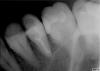

костерико Опубликовано 18 марта, 2010 Автор Поделиться Опубликовано 18 марта, 2010 (изменено) Сходила взяла снимки в эл.виде.Будьте добры посмотрите каналы,как сделаны.И все-таки я не понимаю,не развод ли это был.Где там два канала?И зубы,которые справа и слева от анкерного-их состояние.Если конечно качество подходит.Добавлю 4 снимка,какой лучше не знаю. Изменено 18 марта, 2010 пользователем костерико Ссылка на комментарий

костерико Опубликовано 18 марта, 2010 Автор Поделиться Опубликовано 18 марта, 2010 (изменено) Этот зуб и должен болеть - из двух каналов один недопломбирован,второй незапломбирован вообще.Нужен хороший эндодонтист (не за 2,5 тыщи), потом культевая вкладка и коронка. PS. И пломбу на шестом переделать. Нависающий край.это что то новое........это уже вторая переделка и что опять не переделали хорошо?а все так думают?я сейчас в обморок упаду.вообще зуб уже не болит,хотя,при постукивании по нему,он неприятно чувствителен(((А ТРЕТИЙ РАЗ МОИ КАНАЛЫ ОСИЛЯТ? Изменено 18 марта, 2010 пользователем костерико Ссылка на комментарий

zybnaya feya Опубликовано 18 марта, 2010 Поделиться Опубликовано 18 марта, 2010 это что то новое........это уже вторая переделка и что опять не переделали хорошо?а все так думают?я сейчас в обморок упаду.вообще зуб уже не болит,хотя,при постукивании по нему,он неприятно чувствителен(((А ТРЕТИЙ РАЗ МОИ КАНАЛЫ ОСИЛЯТ? Костерико,вы хоть бы пронумеровали сним. Где ДО ,а где ПОСЛЕ?? Если тот что самый последний,так он мутный и не информативен. Все остальные я так поняла сделаны ДО последнего (второго)вмешательства? Ссылка на комментарий

костерико Опубликовано 18 марта, 2010 Автор Поделиться Опубликовано 18 марта, 2010 (изменено) Костерико,вы хоть бы пронумеровали сним. Где ДО ,а где ПОСЛЕ?? Если тот что самый последний,так он мутный и не информативен. Все остальные я так поняла сделаны ДО последнего (второго)вмешательства?нет,все СНИМКИ СДЕЛАНЫ ПОСЛЕ ПЛОМБИРОВКИ каналов.НА НИХ ГОТОВЫЙ РЕЗУЛЬТАТ.доктор все сделан, потом рентген,сказал все супер. Изменено 18 марта, 2010 пользователем костерико Ссылка на комментарий

zybnaya feya Опубликовано 18 марта, 2010 Поделиться Опубликовано 18 марта, 2010 нет,все СНИМКИ СДЕЛАНЫ ПОСЛЕ ПЛОМБИРОВКИ каналов.НА НИХ ГОТОВЫЙ РЕЗУЛЬТАТ.доктор все сделан, потом рентген,сказал все супер.Если ЭТО окончательная пломбировка,то +10000 к мнению Fury Канал не пролечен до апекса(а их 2) и весь просвет в порах,что свидетельствует о его вустотк в просвете. Очень жаль это говорить-но перелечивать его надо снова Ссылка на комментарий